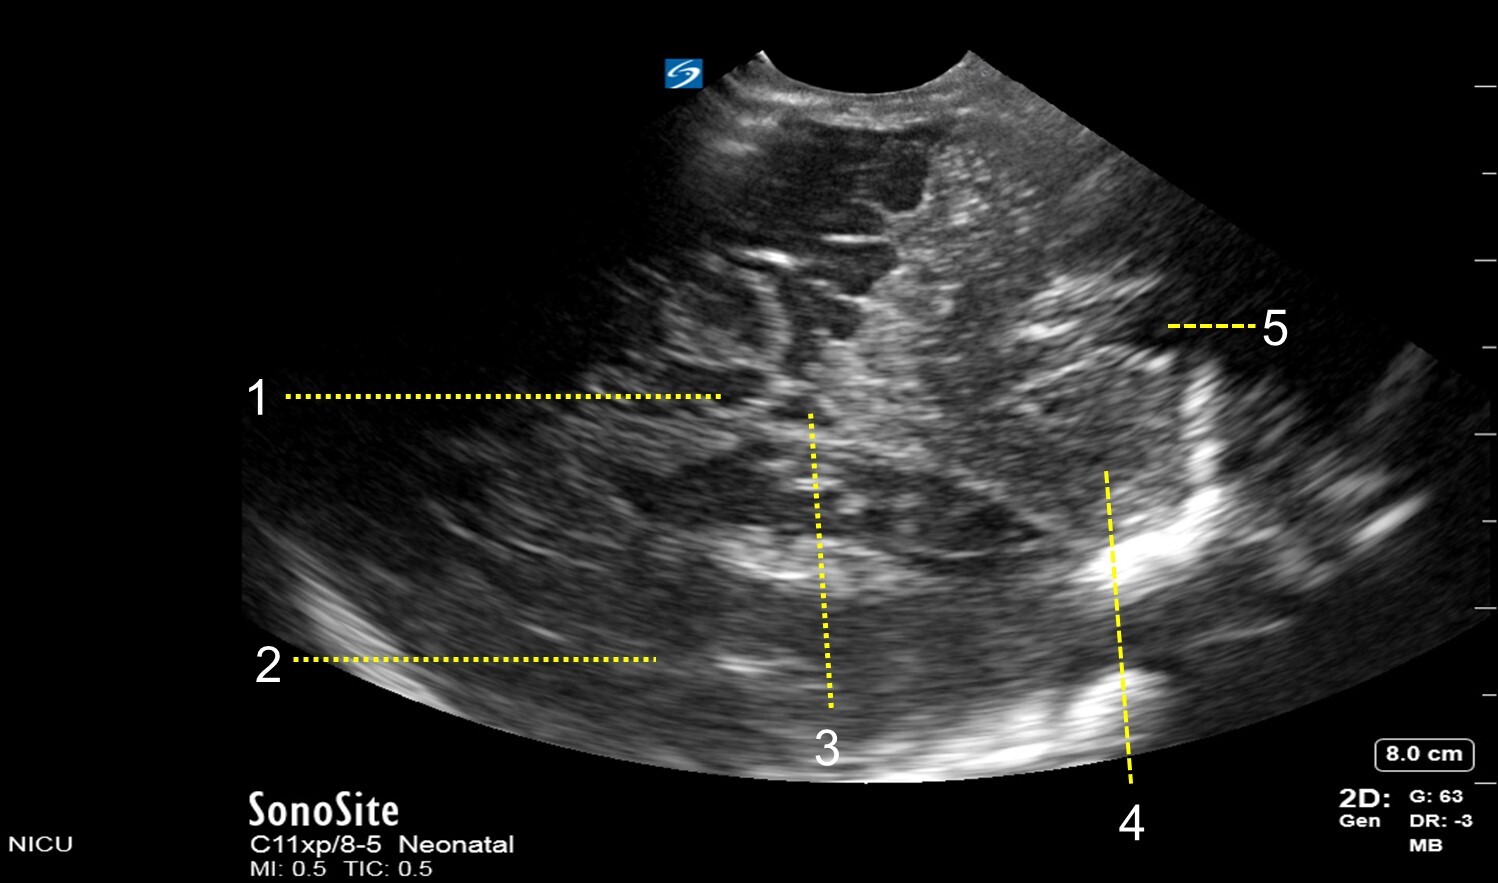

Neonatology Mastoid Fontanel – Mid-Coronal View Image

1. Mesencephalon

2. Parietal Lobe

3. Fourth Ventricle

4. Cerebellar Hemisphere

5. Cisterna Magna